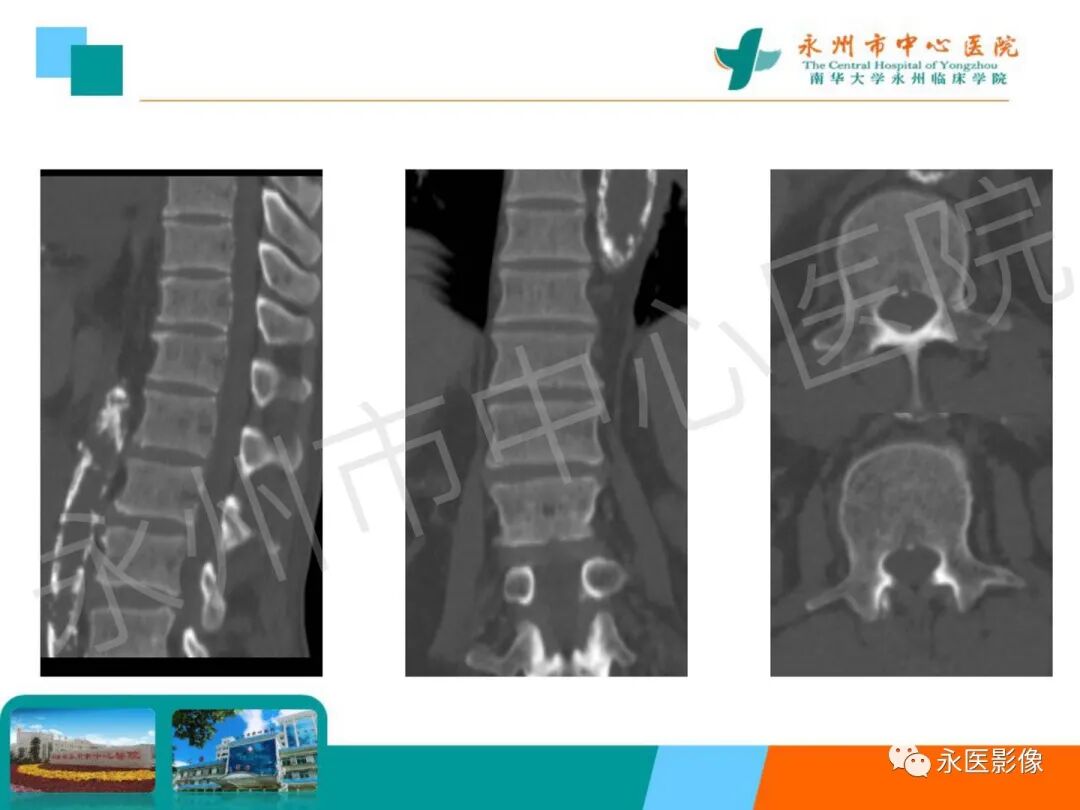

椎体夹心饼征:在X线平片上,胸腰椎椎体上、下缘终板各形成一条硬化带,每个椎体中心可见一条透明带,相互并行的硬化带和透明带与英式橄榄球衫(rugby sweater)上的条纹类似,西方学者称之为橄榄球衫椎体(rugger jersey spine)。这种两条硬化带中夹一条透明带的表现与中国的夹心饼亦相似,国内学者称之为夹心饼征。椎体终板上下缘的硬化带代表过多的骨样物质沉积,虽然它们的骨化并不充分,但这些骨样组织与正常椎体相比密度增加,在Ⅹ线照片上显示为不透光性,常为慢性肾衰竭所致